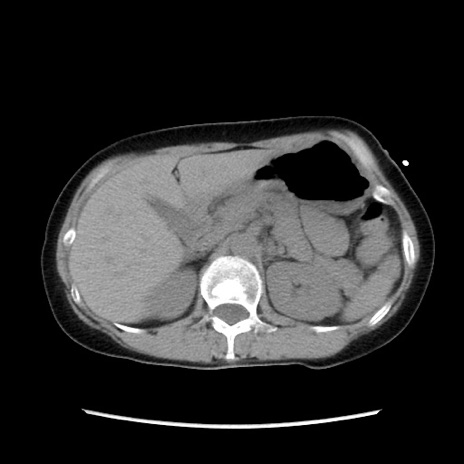

症例32(横断像)

【症例】40歳代 女性

【主訴】上腹部痛、嘔気・嘔吐

【現病歴】約9時間前頃から急に上腹部痛、嘔気、嘔吐が出現。改善しないため救急要請。

【既往歴】子宮頚癌(広汎子宮全摘術、放射線療法)、腸閉塞

【身体所見】腹部:平坦、軟、腸雑音亢進、上腹部を中心に腹部全体に圧痛あり。

【データ】WBC 8400、CRP 0.03